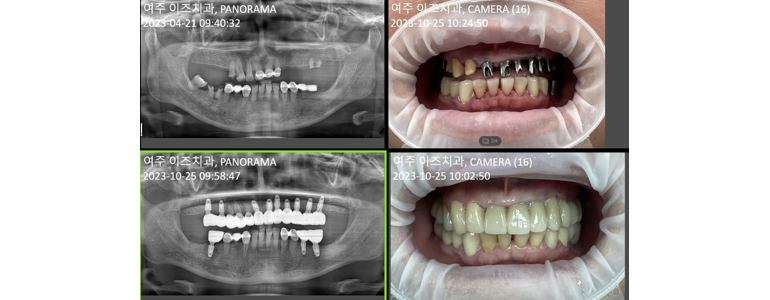

여주이즈치과의원

여주이즈치과의원 은 최첨단 CT 장비와 정밀한 진료 로, 안전하고 신속한 치료를 제공하는 치과입니다.

위치: 경기 여주시 세종로 10 영무빌딩 201호

전화번호: 031-881-2897

서비스: 임플란트, 사랑니 발치, 보험틀니, 소아치과, 치과교정